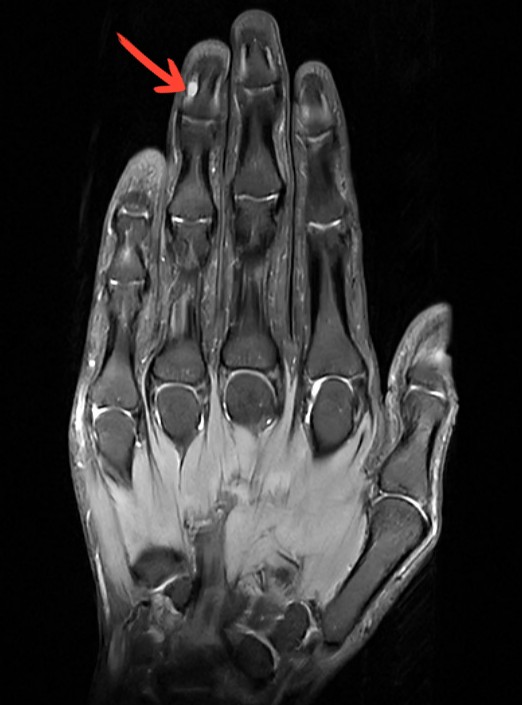

甲下血管球瘤是一种起源于血管球体的良性肿瘤,常出现在手指或脚趾的甲床下,较少引起指甲外观异常,通常可通过手指的磁共振(MRI)检查确诊。虽然它是良性的,但带来的疼痛却让人难以忍受,尤其是对温度变化和压力异常敏感。

局部变色:甲床下可能出现蓝红色的小斑点(有时可通过在暗室下光照指腹自行自检)。如果你的手指或脚趾经常莫名其妙地疼痛,尤其是天气变冷时更加严重,千万别忽视,这可能是甲下血管球瘤的信号!可到医院做个手指/脚趾的MRI明确诊断。手指磁共振(MRI)检查